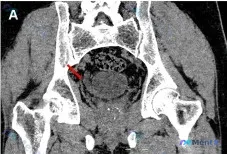

患者是做PCNL(经皮肾镜取石术)的情况,术前CT冠状位首先关注到了右侧输尿管扩张,但仔细扫骨窗的时候发现了另一个关键问题:

- 右侧坐骨/髂骨区域(靠近髋臼后方) 可见明显的骨质连续性中断,是一条斜行的透亮线,边缘相对锐利,没有明显硬化边;

- 其余盆骨、髋关节在该层面没有明显脱位、其他骨质破坏或增生;

- 骨窗下软组织分辨率有限,没有看到明确异常钙化/肿块,但不能排除血肿。